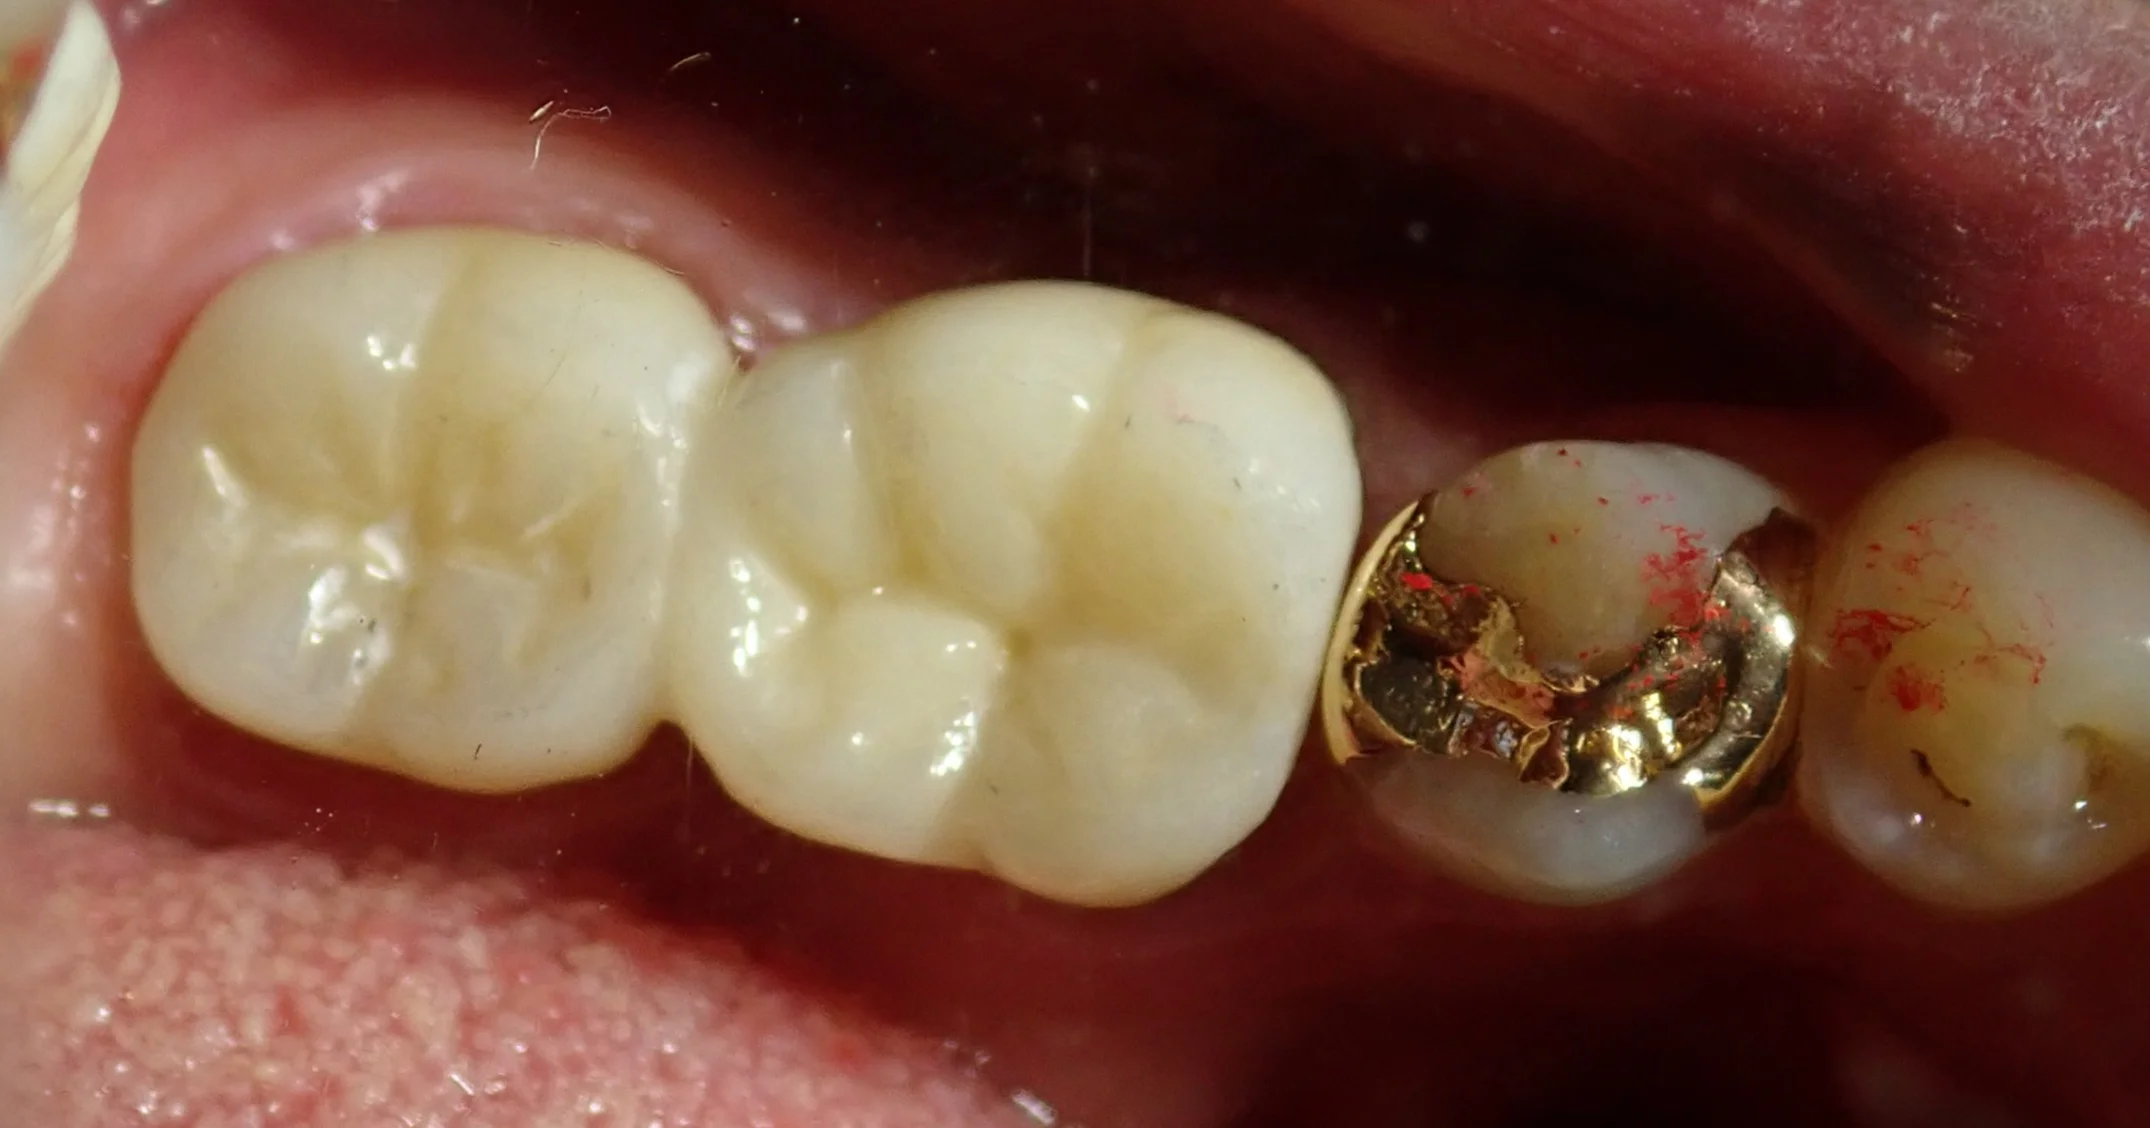

無事に神経の治療も終わり、後ろの根の抜歯後の傷も問題なく治ったため、最終的な被せ物に移行することとなりました。

で、セラミックを装着した模型がこちらです。

見た感じ普通に2本の歯っぽく見えるように仕上げてもらいました。

歯がない所謂「ダミー部」については歯間ブラシやブリッジ用のフロスを通せるように若干の隙間を作っています。

実際のお口の中の写真がこちらです。

着けた後がこちらですね。

適合良く大きな調整なく綺麗に入ってくれました。

普通歯根破折で抜歯を行う際には、問題の無い根まで抜いてしまう事が結構ありますが、それをするとブリッジを作る際に一つ手前の歯まで大きく削る羽目になってしまいます。

残せるのであれば残してあげたほうが、10年20年後に見た時に圧倒的に有利かと思います。

今回の方は保険診療でのやり直しに嫌気がさしたとのことで自費診療のセラミックで行いましたが、この治療方法は保険適用内ですので、普通に保険の金属のもので仕上げることも出来ます。